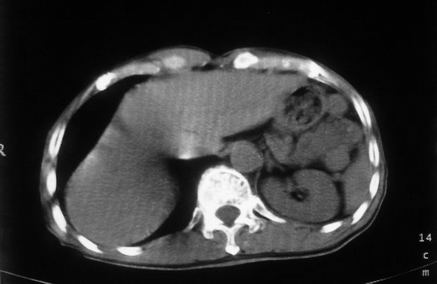

男,66岁,贲门ca术后一年,喝了5、6杯水了。怎么描述跟诊断啊